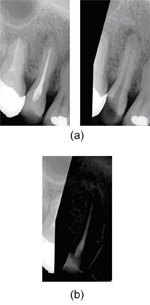

得られた共通領域に対して位相限定相関法を用いて類似度を求めます。位置や角度、ひずみが補正され、共通領域を抽出しているので、同じ人のほぼ同じ位置を撮影したエックス線写真であれば、鋭い相関ピークが現れます。もし違う人のものであれば、位置などを合わせたとしてもピークが現れません。そこで、開発したシステムでは、このピークの高さを類似度として用いています。ピークは、最大値が1、最小値が0であることより、1に近い値となれば同じ人であると言えます。図5が位相限定相関法を用いて画像の類似度を評価した例になります。図5の(a)が同じ人の場合、(b)が違う人の場合となります。

画像の類似度評価:

(a)同じ人の場合

(b)違う人の場合